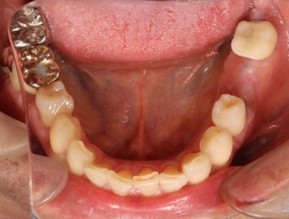

20代 男性

治療前

治療後

治療後- リスク・副作用

- 20代/男性

- 患者の具体的な症状

- 1年前に左上12 右上1の根の治療をし、その後放置していたら、左上2が破折した。

左上2インプラント補綴 左上1右上1オールセラミック装着。

歯根破折と虫歯による痛み、審美障害を主訴として来院。 - 検査方法

- コーンビームCT、レントゲン撮影

- 診断結果

- 左上2 歯根破折

- 治療詳細

- 左上抜歯後、インプラント埋入1本

骨造成あり 局所麻酔

インプラント治療後、左上1右上1セラミック修復2本 - 通院回数

- 9回

- 治療期間

- 12か月